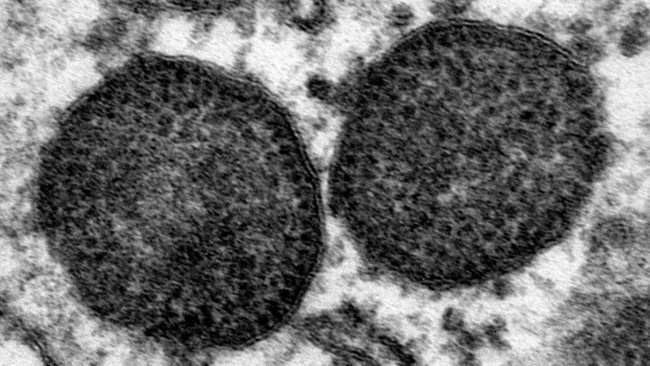

It has been 20 years since wasting disease appeared. Are vaccines still effective? Has the disease's epidemiology changed? Should we be concerned about new PCV2 strains or PCV3?

In the years since the PCV-2 vaccine was introduced to solve the enormous problem caused by circovirus, what do you think has changed and how does it affect farms?

The decrease in PCV2a and PCV2b genotypes over time and the increase in PCV2d in 2012 may be due more to other, unknown, factors than to immunological selection resulting from PCV2a-based vaccination.